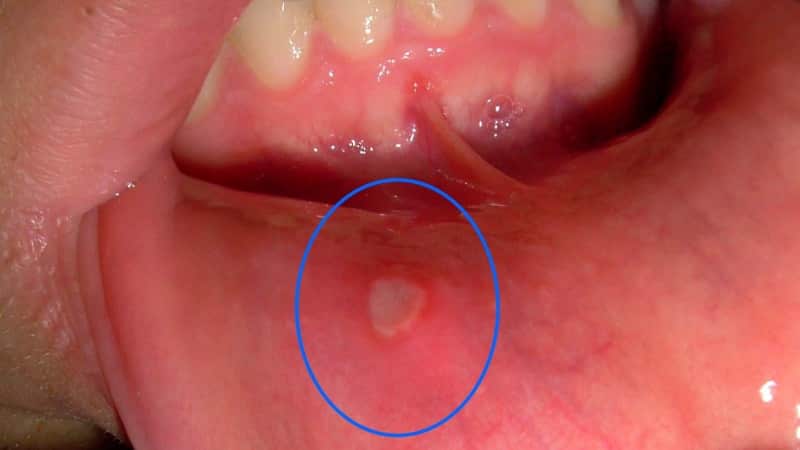

При осмотре ротовой полости у ребенка можно заметить первые признаки различных заболеваний. Язвочки на слизистой оболочке становятся видимыми при открывании рта и оттягивании нижней губы.

Если вы заметили язвы, важно отнестись к этому серьезно и обратиться к стоматологу или педиатру.

Хроническое афтозное состояние проявляется образованием одиночных афт, сопровождающихся повышенной температурой и головной болью. Появление заболевания связано с нарушениями иммунной системы, аллергическими реакциями и заболеваниями желудочно-кишечного тракта. Симптомы чаще всего проявляются в передней части ротовой полости, где слизистая может часто повреждаться. Небольшие образования окружены красным ободком и имеют серо-белый цвет. При прикосновении к ним возникает боль.